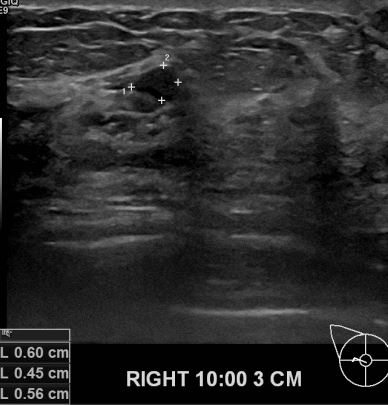

상기환자 1년전 타원서진료받으시고 경과관찰차 내원하신 40대여성 분으로

초음파 진료이후 우측유방에 의심스러운혹 조직검사후 유방암 진단 되셨읍니다